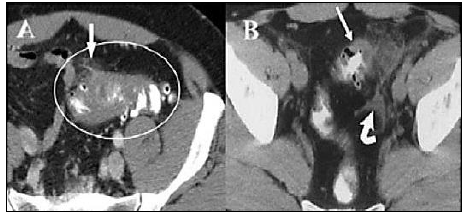

“Mulher, 52 anos, comparece ao pronto-socorro com dor em fossa ilíaca esquerda há 1 dia, de caráter progressivo, mas de média intensidade. Ao exame, descompressão-brusco dolorosa postiva. Apresenta o seguinte achado de TC sem contraste”.

Trata-se, provavelmente, de